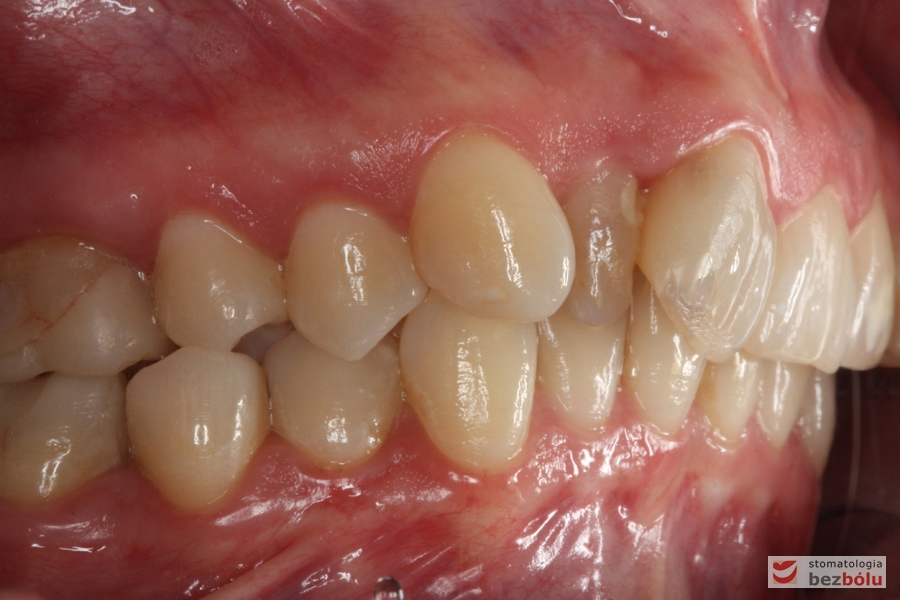

Pacjentka lat 26 zgłosiła się do gabinetu celem korekcji uśmiechu. Głównym zmartwieniem były problemy estetyczne, które znacznie wpływały na jakość życia pacjentki. Wykonano leczenie zachowawcze zębów oraz analizę cefalometryczną i analizę modeli diagnostycznych. Zaplanowano leczenie aktywne aparatem DAMON dla szczęki i żuchwy, które trwało 2 lata. Po fazie leczenia aktywnego rozpoczęto leczenie retencyjne z użyciem szyny tłoczonej dla szczęki i retainera stałego dla żuchwy.